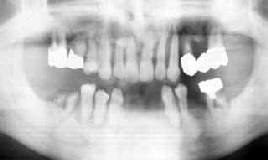

| 最悪→歯周疾患・二次カリエス・根管治療 57歳 女性 |

使える歯を最大限残して連結固定 |

初診時口腔内およびX線所見:

装着された補綴物の形跡から、治療に多くの労力を費やしたにも関らず、カリエス・歯周疾患

伴に進行が著しい。「全部抜いて、総入れ歯」と言われてから歯医者に行くのが怖くなって数年間

放置していたとのことである。歯槽骨と全く接していない歯も随所に認められる。

処置および経過:

比較的骨植の良好な下顎に対しては、Fop+Nd/YAG LASER(根面処理)を施行することとし、

上顎は手術不能と判断してルートプレーニングバーによる根面処理を行ったのち連結固定。

欠損部分にかんしては、インプラントの含みをもたせて一旦は義歯による咬合回復を計った。

約10ヵ月の治療期間を経て、メインテナンスに移行。

考察:

臼歯部の支えを失った上顎前歯部の末路は悲惨です。手術をして進行をくい止めたとしても、

過剰な咬合圧による破壊を阻止することはできない。臼歯部インプラントと連結することにより

多少延命を図ることは可能だとは思いますが、保険の効かない現状では出費と延命効果との

バランスがとれません。

感想:

上顎って、咬合方向が悪く、歯槽骨が緻密でないので条件的に不利?

もう少し早く来院していれば・・・・・。